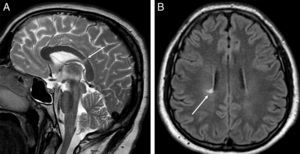

Se realizaron varias RM craneales de control, en las que se demostró una leve progresión de la enfermedad pero sin repercusión clínica, manteniéndose el diagnóstico de presunción de EM. Seis años después de este episodio, el paciente presentó un cuadro de tos y disnea. En una radiografía de tórax (fig. 2A) se observó un ensanchamiento del mediastino, un aumento del tamaño de los hilios pulmonares y una afectación intersticial, por lo que se decidió realizar una TC de tórax ante la sospecha radiológica de posible sarcoidosis. En la TC se confirmó la presencia de múltiples adenopatías en mediastino y en ambos hilios pulmonares (fig. 2B), así como una severa afectación intersticial (fig. 2C). El diagnóstico radiológico de presunción fue el de sarcoidosis (estadio II), que fue confirmada histológicamente mediante una biopsia transbronquial. Tras la instauración del tratamiento con corticoides sistémicos e inhalados (en pauta descendente) el paciente mejoró desde el punto de vista clínico y radiológico (fig. 2D). Una nueva RM de cráneo de control mostró estabilidad de las lesiones con respecto al último estudio.

Radiografía de tórax (A) en la que se observa un ensanchamiento mediastínico, un aumento del tamaño de los hilios pulmonares y un patrón intersticial. La TC de tórax confirma la presencia de adenopatías mediastínicas de tamaño significativo, una afectación hiliar bilateral (B, reconstrucción coronal con contraste intravenoso) y del parénquima pulmonar (C, imagen axial en ventana de pulmón). Radiografía de tórax (D) obtenida 6 meses después del comienzo del tratamiento con corticoides que muestra una normalización de los hallazgos.